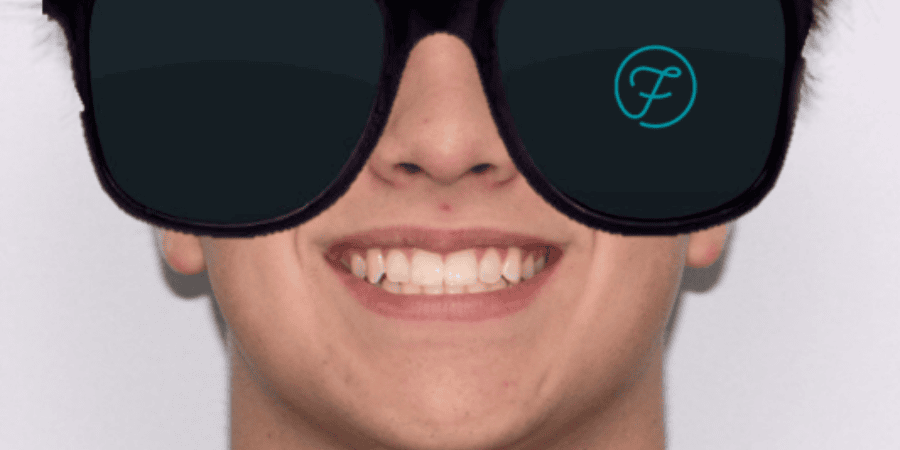

After